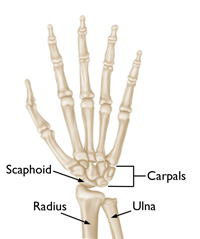

AnatomyThe wrist is formed by the two bones of the forearm—the radius and the ulna—and eight small carpal bones. The carpal bones are arranged in two rows at the base of the hand. There are four bones in each row.

The scaphoid bone is one of the carpal bones on the thumb side of the wrist, just above the radius. The bone is important for both motion and stability in the wrist joint. The word "scaphoid" comes from the Greek term for "boat." The scaphoid bone resembles a boat with its relatively long, curved shape.

The scaphoid is one of the small carpal bones in the wrist.

Reproduced with permission from JF Sarwark, ed: Essentials of Musculoskeletal Care, ed 5. Rosemont, IL, American Academy of Orthopaedic Surgeons, 2016.